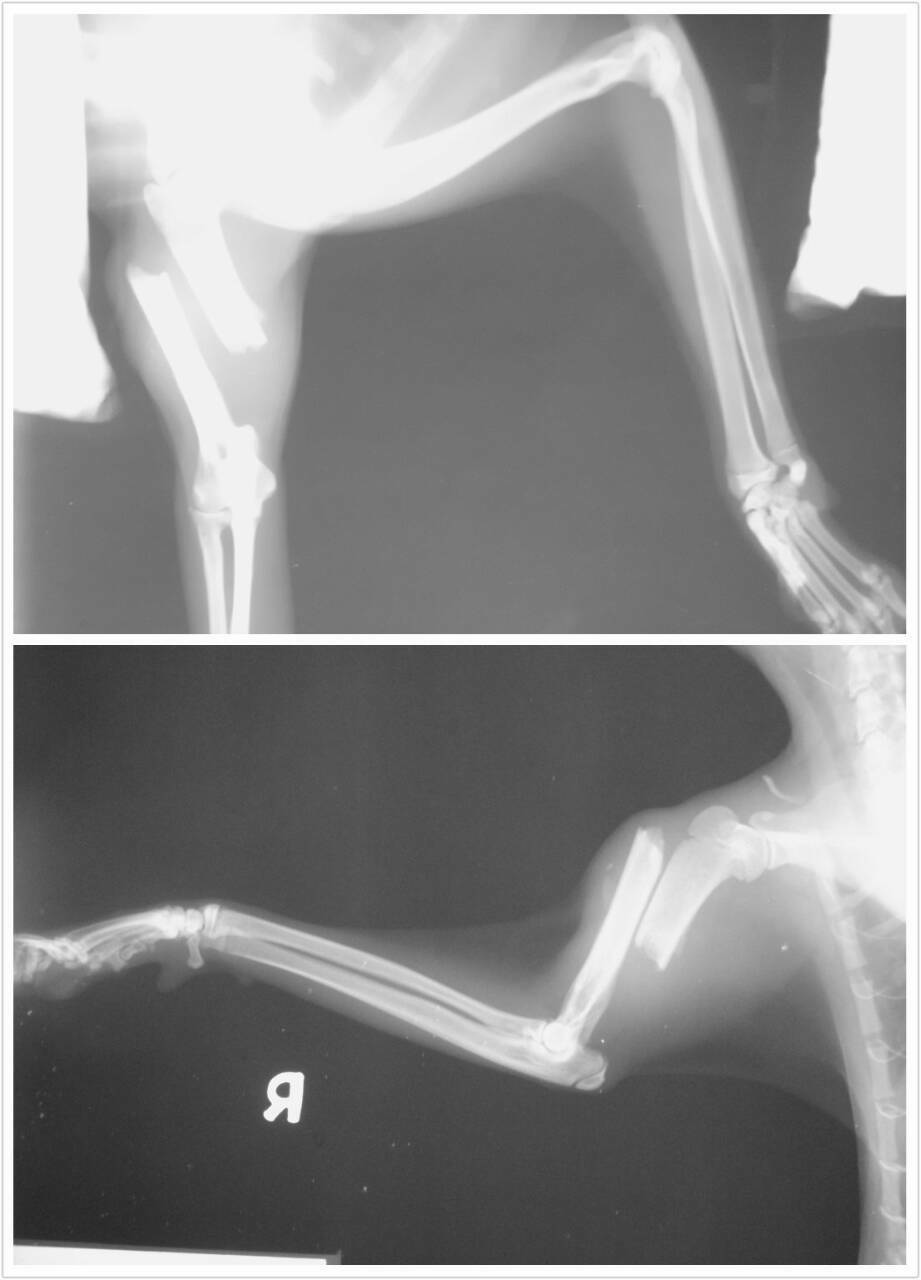

主題: 高雄壽山收容所醫務室攔截既將被安樂之花花(鼻氣管炎,右後腳外傷,右前腳膊骨斷裂非常嚴重) 申請者姓名: 張婷俞 花色: 申請日期: 2014-07-02 22:42:49 申請者部落格: 申請者臉書網址: 所在縣市/合作醫院: 高雄市/樂生動物醫院 治療費用: 28080元 需求人數: 30人 已結案 (2014-08-05 10:58:14) 報名人員: 小四 x2(已付款)、YiLing Li(已付款)、阿米(已付款)、吳佳祐(已付款)、胡嘟嘟(已付款)、鄧莉臻(已付款)、Kith Shiu(已付款)、Joanna Hu(已付款)、Sybil Huang(已付款)、Riona Chiu(已付款)、Egg(已付款)、Victoria Liou x2(已付款)、vivian(已付款)、Alice Tsai(已付款)、Victoria Liou x2(已付款)、Gina Du(已付款)、Sylvia x2(已付款)、阿曄(已付款)、Jean Lin(已付款)、Kuen-Lin Tsai(已付款)、凌波煙嵐(已付款)、Yaruh Fu(已付款)、有貓真好(已付款)、曾昭瑜(已付款)、CrystalBall x2(已付款)、 候補人員: 動物病情說明: 5/8上高雄壽山收容所救援2隻既將被安樂需要醫助的貓咪,花花跟白白。花花有脫水及眼鼻分泌物,咳嗽等鼻氣管炎的症狀且右後腳有外傷,右前腳跛行不願著地,經醫生鎮定照X光檢查,發現其上膊骨已斷裂,需手術治療,但因血液檢驗呈現白血球偏高,加上其嚴重鼻氣管炎的狀況,初步會先給藥及輸液治療,待病情穩定後再進行骨科手術。花花原本已結紮剪耳。

原本花花預估費用:有脫水及眼鼻分泌物,咳嗽等鼻氣管炎的症狀且右後腳有外傷,右前腳跛行不願著地,經鎮定照X光檢查,發現其上膊骨已斷裂,需手術治療,但因血液檢驗呈現白血球偏高,加上其嚴重鼻氣管炎的狀況,初步會先給藥及輸液治療,待病情穩定後再進行手術,初步醫療預沽如下:

4.X光檢驗 300*2=600

4 X光檢驗 300*4=1200